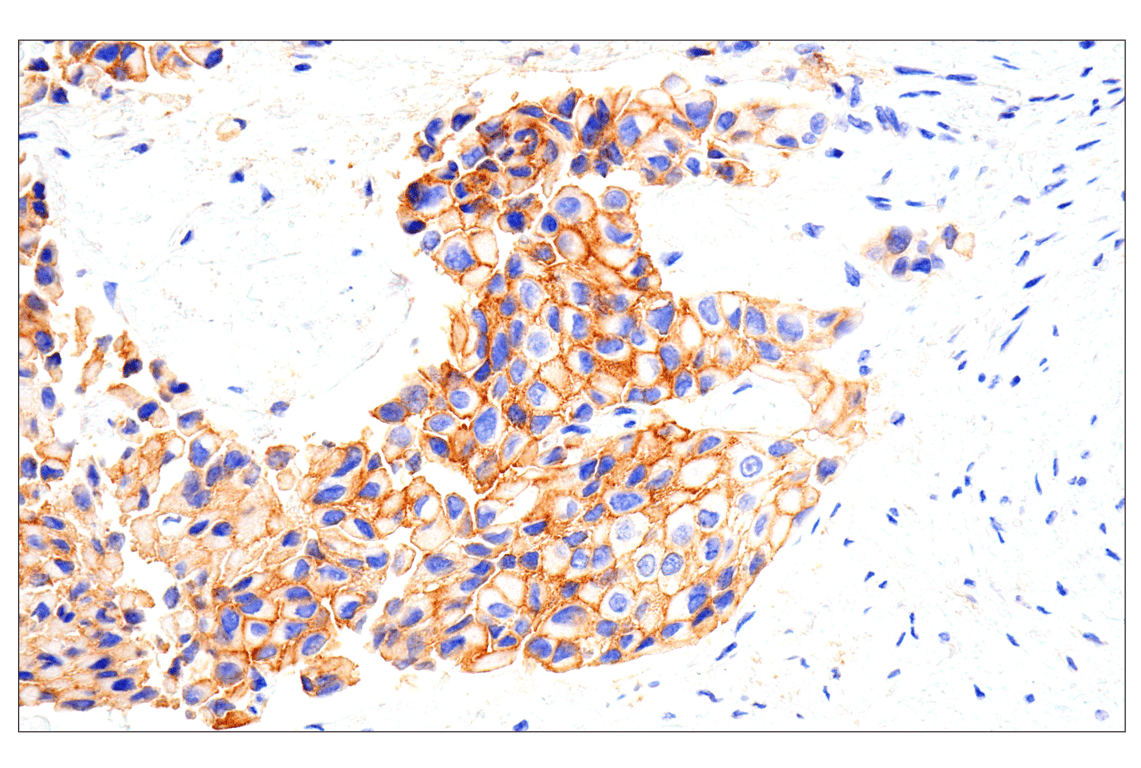

Immunohistochemical analysis of paraffin-embedded human non-small cell lung carcinoma using EphA2 (D4A2) XP® Rabbit mAb.

Immunohistochemistry Image 1: EphA2 (D4A2) Rabbit Monoclonal Antibody